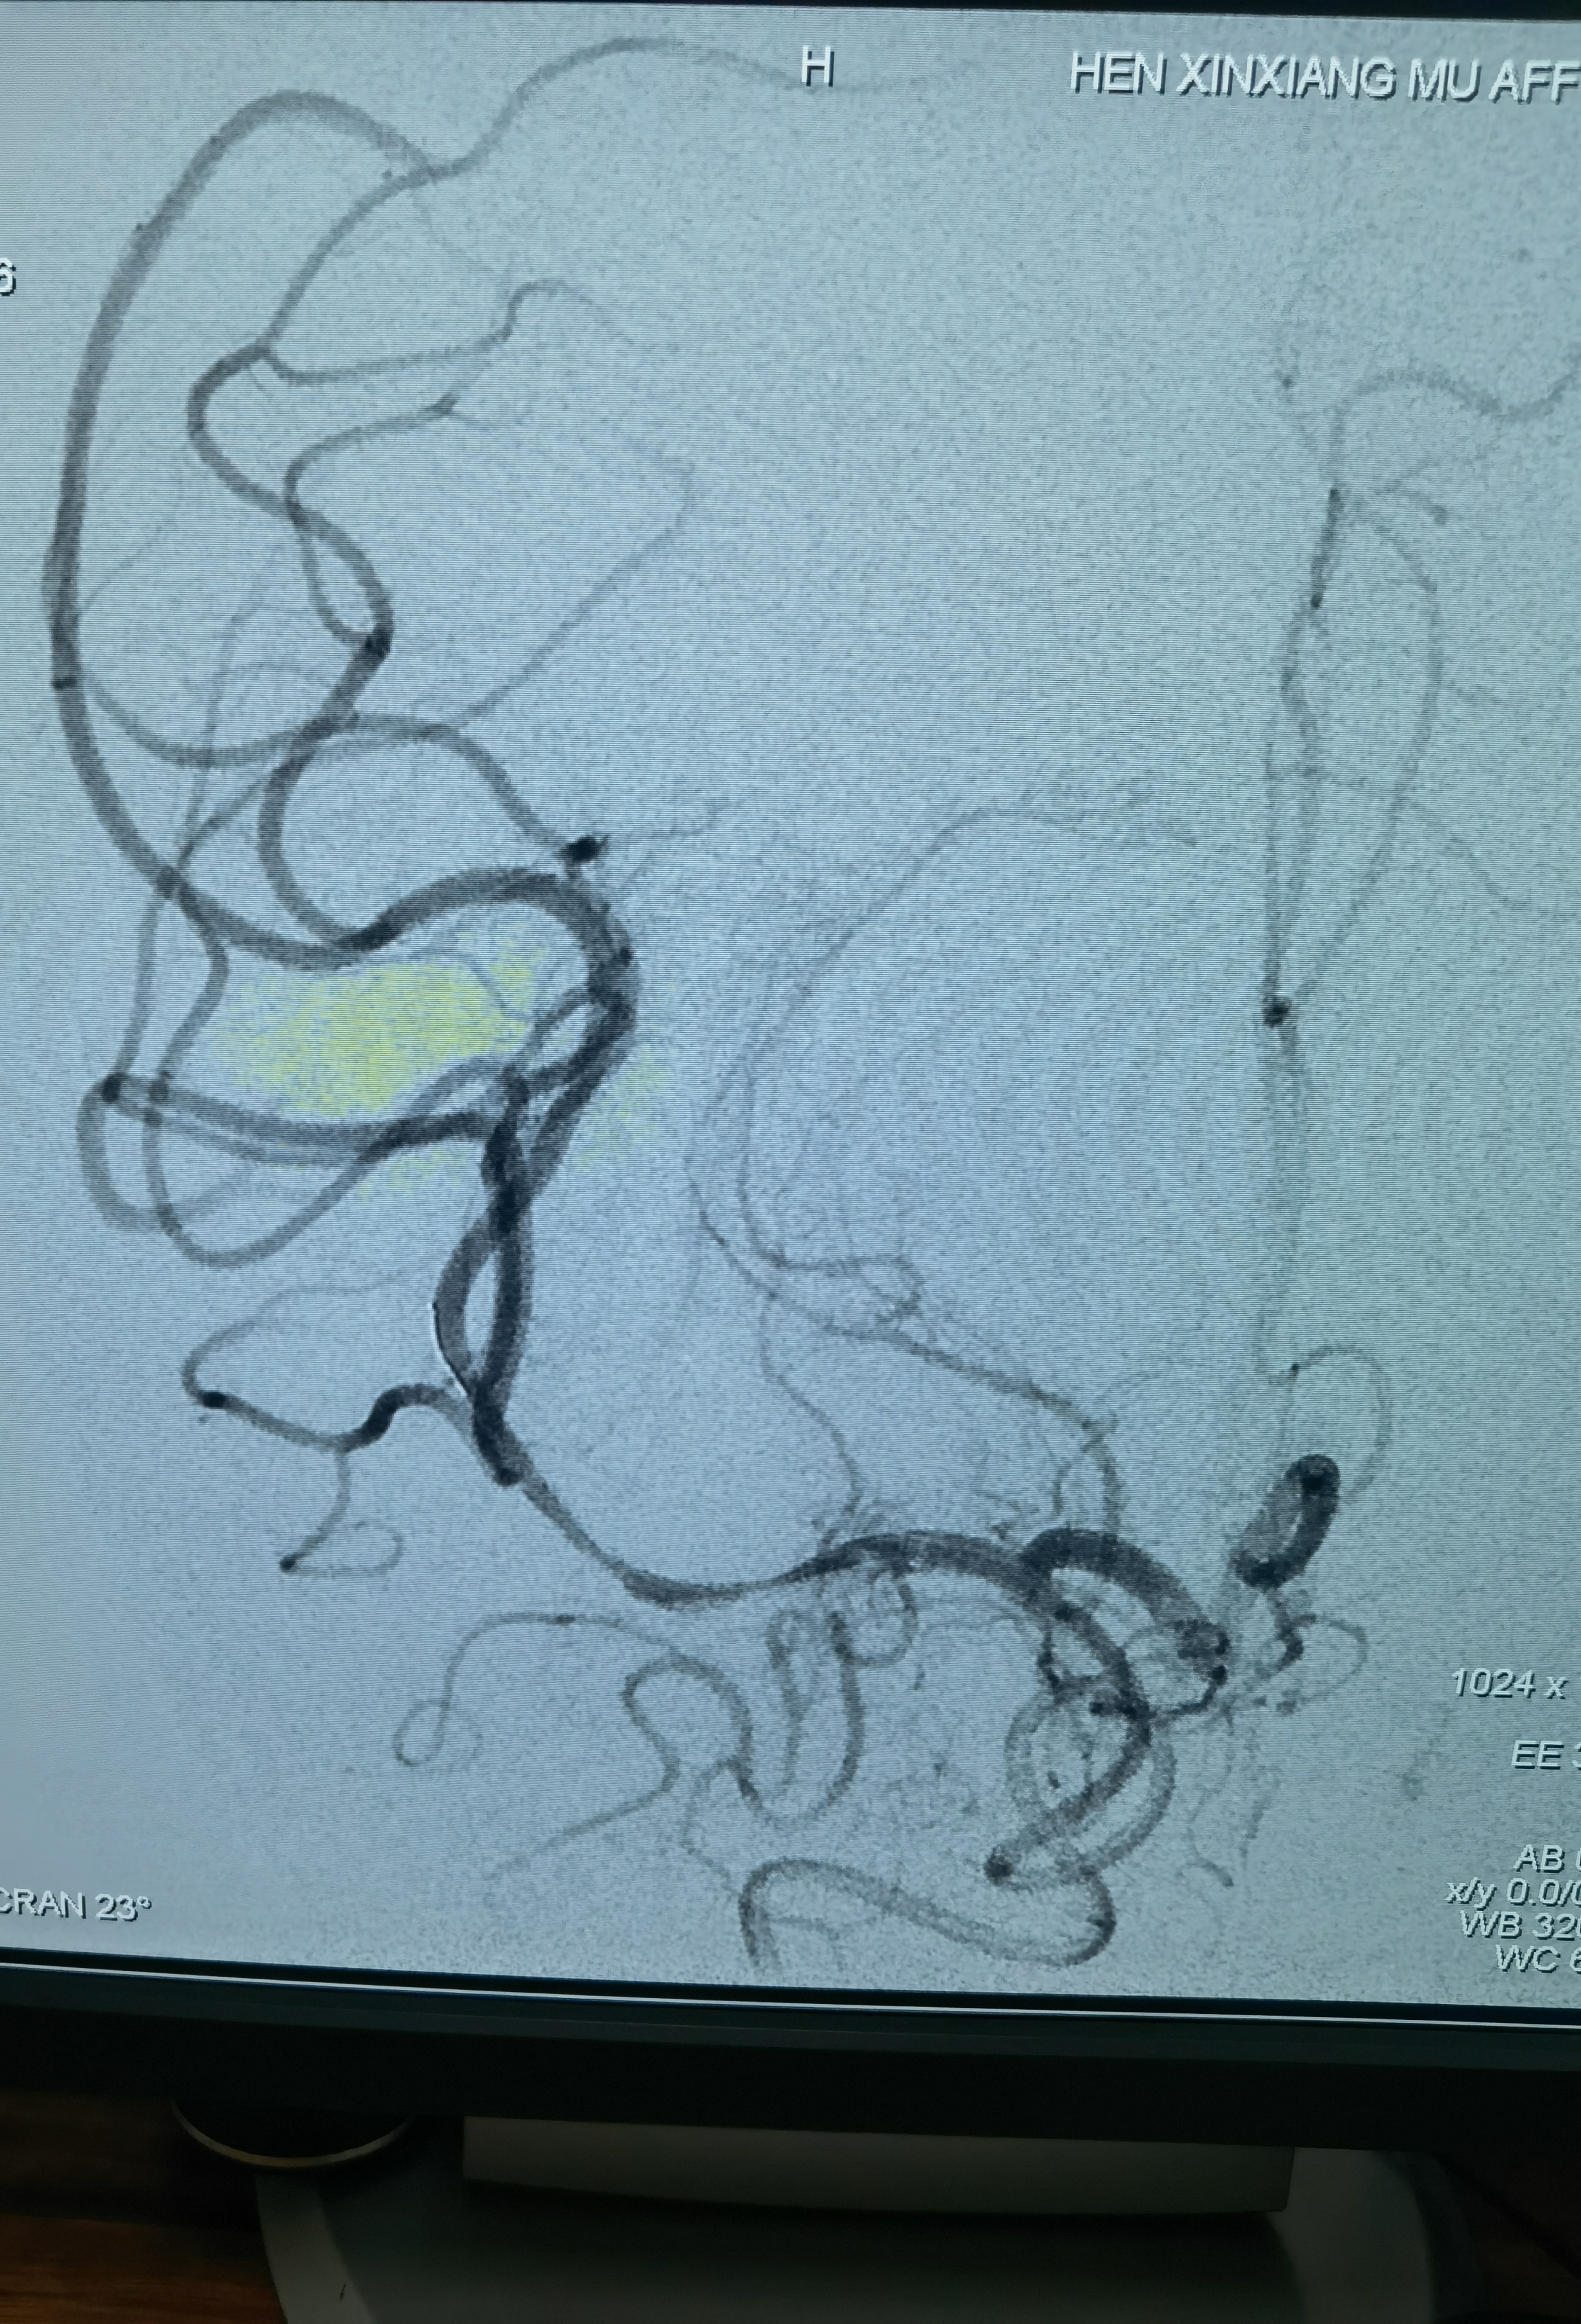

中间再上一禾木6F127抽吸导管,造影

先上抽吸导管抽吸一把,抽出一小块血栓!造影没有通!

上取栓支架取栓,还是没通!

第一支架取栓后造影!